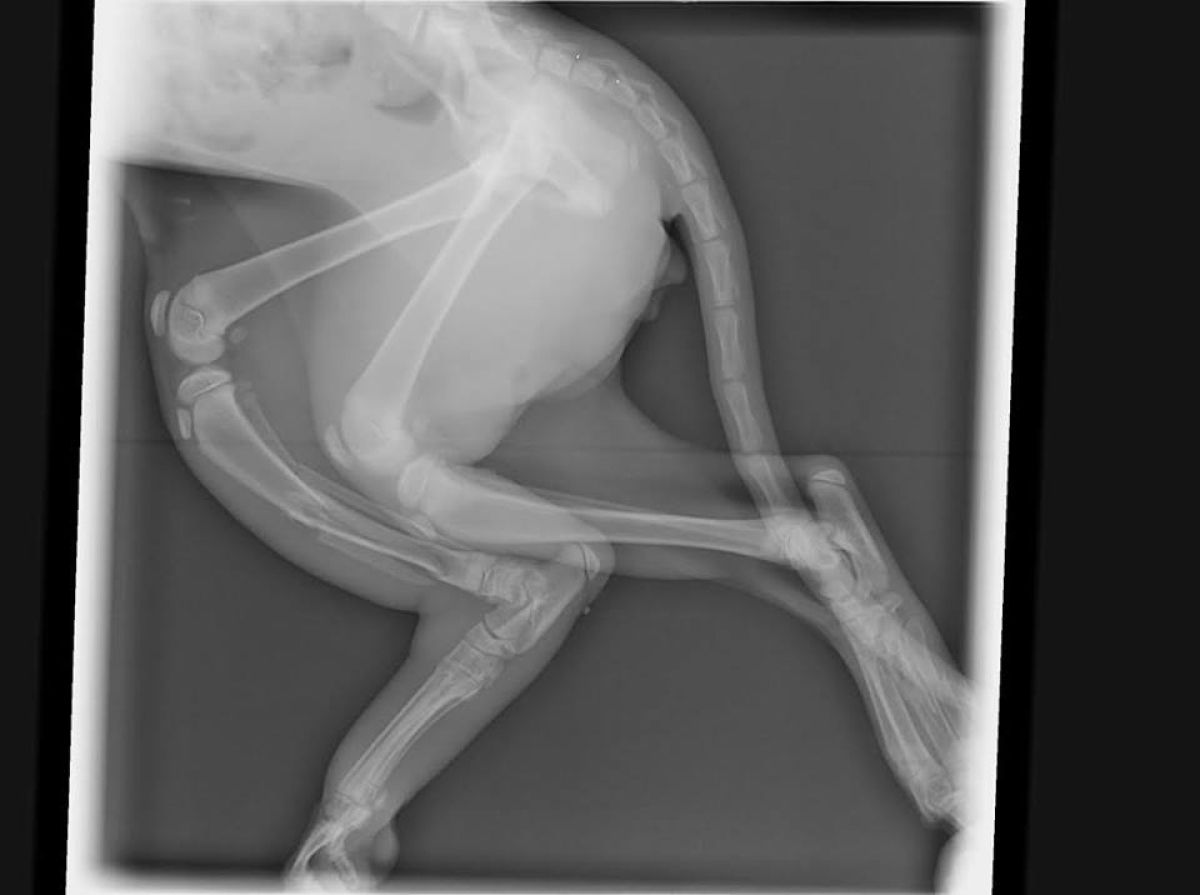

Prvi, oranžno-bele barve, je bil najden na Partizanski ulici, kjer se je potikal okoli blokov, dokler ga ni opazil prijazen gospod in je o tem obvestil društvo. »Muca je po vsej verjetnosti za tačko zagrabil pes, saj so bile vidne sledi ugriza. Stegnenica je bila zdrobljena,« nam je povedala Dajana Vodnjov iz društva. Druga muca, ki ima sivo dlako, je bila najdena v Mislinjski Dobravi. »Hud zlom stegnenice je posledica udarca avtomobila. Imela je srečo, da so jo našli prijazni ljudje, ki ji bodo nudili dom, poimenovali so jo Luna,« je razložila Dajana. Obe muci sta potrebovali pomoč in po RTG-posnetkih je bila kot najboljša možnost, zaradi starosti in še mehkih kosti, predlagana osteosinteza z zunanjim fiksatorjem.

»Zahteven poseg, ki ima obsežnosti primerno tudi ceno in bo društvo stalo okrog 400 evrov za vsako muco. S posegom lahko muci obdržita zadnjo tačko, zato smo se odločili, da jima operacijo omogočimo,« obrazloži Vodnjova. Muc iz Prežihove je bil operiran prvi, saj je poseg najbolje opraviti čim prej, in se zaenkrat dobro počuti. Muc bo po nekaj dneh oskrbe v hospitalu na veterini, sprejet v društveno oskrbo, saj potrebuje redno nego. Tudi Luna je bila operirana in je dobrega počutja, zdaj se vrača v svoj novi dom.